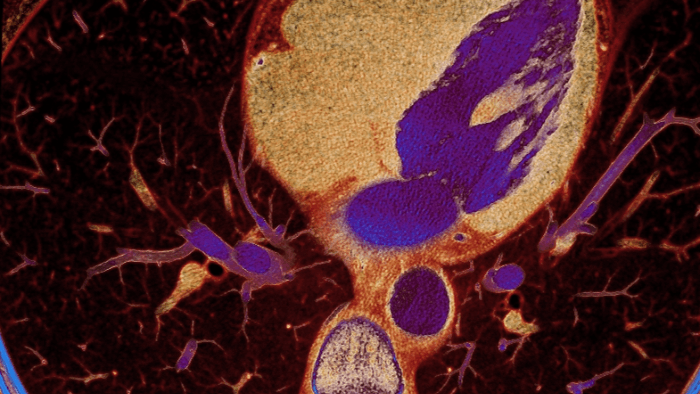

Unlike traditional CT images, spectral-detector CT images capture spectral information 100% of the time —without special planning or set-up. That means you can analyze the spectral data in any image retrospectively, using a variety of spectral viewing tools. You can, for example, adjust the monoenergetic level or get Zeffective maps.

Can you see the difference?

Move the slider to reveal spectral results when compared to conventional CT.

Spectral detector simultaneously absorbs and differentiates high and low energy from a single polyenergetic X-ray beam. Spectral results are acquired within a single scan without the need for special modes.

Detector-based spectral CT simultaneously absorbs high and low energies in the same time and space.